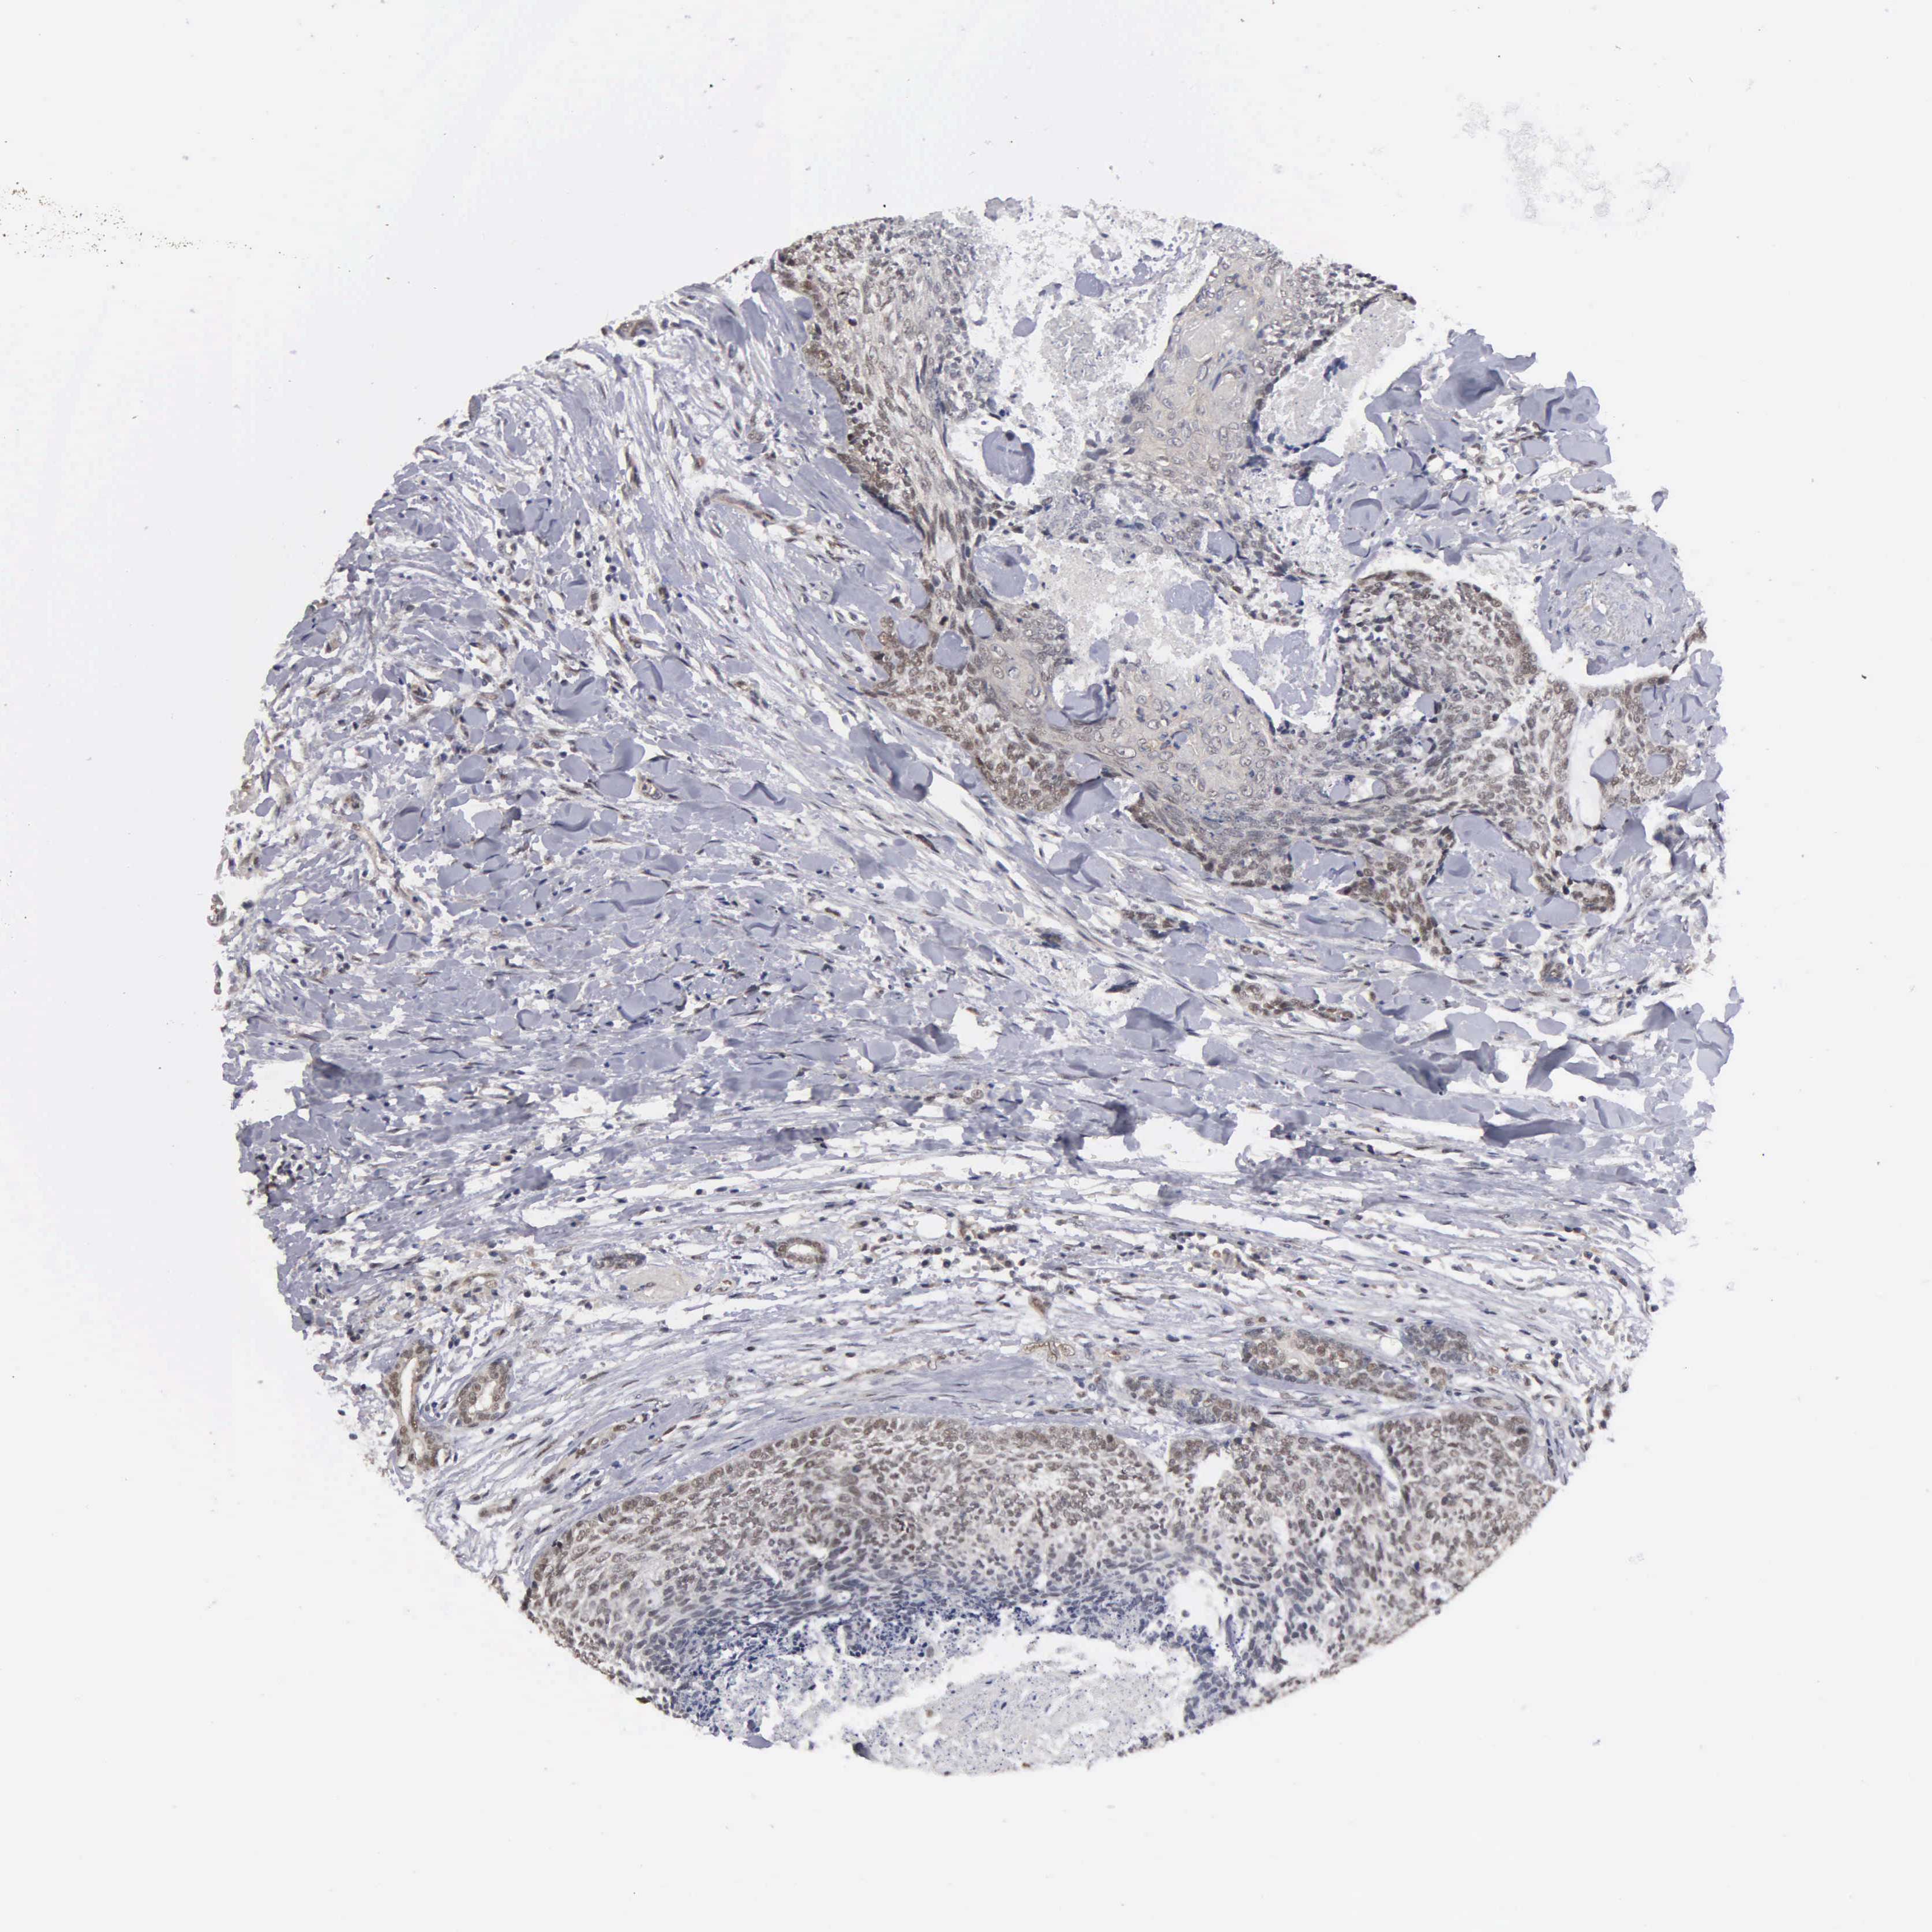

HEAD AND NECK CANCER - Protein expressioni

A mouse-over function shows sample information and annotation data. Click on an image to view it in a full screen mode. Samples can be filtered based on level of antibody staining by selecting one or several of the following categories: high, medium, low and not detected. The assay and annotation is described here.

Antibody stainingi

Antibody staining in the annotated cell types in the current human tissue is reported as not detected, low, medium, or high, based on conventional immunohistochemistry profiling in selected tissues. This score is based on the combination of the staining intensity and fraction of stained cells.

Each image is clickable and will lead to virtual microscopy that enables deeper exploration of all samples and also displays staining intensity scores, fraction scores and subcellular localization as well as patient and tissue information for each sample.

Antibody HPA005732

Squamous cell carcinoma, metastatic, NOS